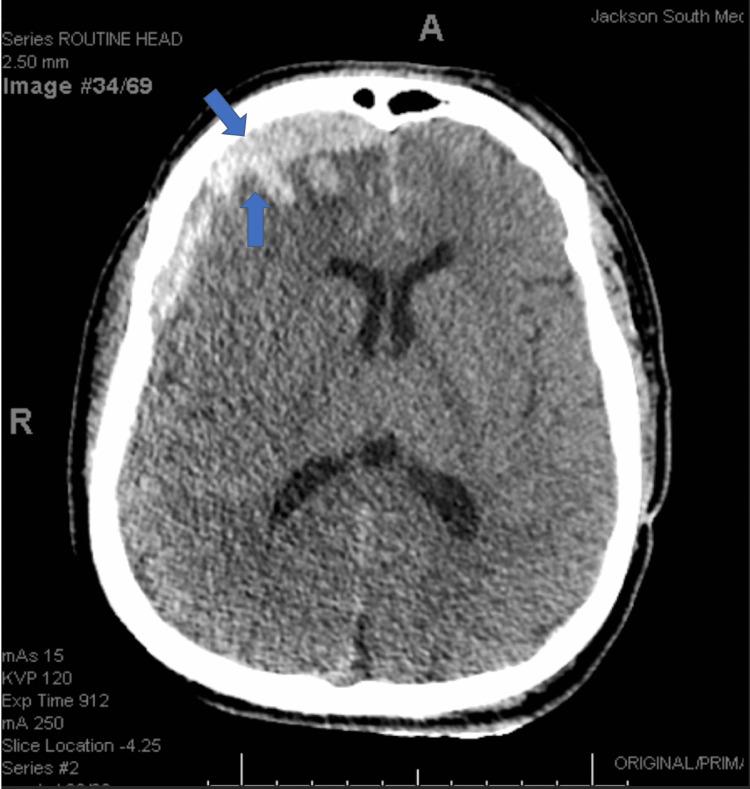

Patients with achondroplasia often present with anatomical abnormalities and altered cardiopulmonary physiology that significantly increase their perioperative risk for cardiovascular and respiratory complications (e.g., worsening ventilation-perfusion mismatch, imminent desaturation, difficult airway). We describe a 34-year-old achondroplastic male presenting with altered mentation following a traumatic subdural hematoma that necessitated emergent craniotomy evacuation. Initial attempt at intubation was complicated by rapid desaturation and bradyarrhythmia. Subsequently, the patient went into cardiac arrest requiring cardiopulmonary resuscitation. A laryngeal mask airway (LMA) was secured and fiberoptic intubation was achieved in succession. Following return of spontaneous circulation (ROSC), a repeat CT scan showed the subdural hematoma to be stable in size and neurosurgery opted to delay his surgery for conservative management and close monitoring. This case highlights the unique airway challenges and anesthetic considerations in management of achondroplastic patients.

软骨发育不全患者常伴有解剖结构异常和心肺生理改变,这显著增加了他们围手术期发生心血管和呼吸并发症的风险(如通气/血流不匹配加重、即将出现的血氧饱和度下降、气道困难)。我们描述了一名34岁的软骨发育不全男性患者,因创伤性硬膜下血肿导致意识改变,需要紧急开颅血肿清除术。初次插管尝试因血氧饱和度迅速下降和心律失常而变得复杂。随后,患者发生心脏骤停,需要进行心肺复苏。成功置入喉罩气道(LMA)并相继完成纤维支气管镜插管。自主循环恢复(ROSC)后,重复CT扫描显示硬膜下血肿大小稳定,神经外科选择推迟手术,进行保守治疗和密切监测。该病例突出了软骨发育不全患者气道管理中独特的挑战和麻醉注意事项。